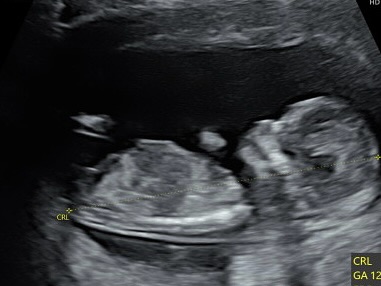

至於現在的狀況,吳怡萱表示,目前懷孕4個月,與先生都開始期待每次產檢照超音波,聽著心跳、看著孩子在肚子裡活潑亂動的模樣,就越來越期待碰面的時刻,「希望吳花果能平安、健康的長大。期待年底見!」